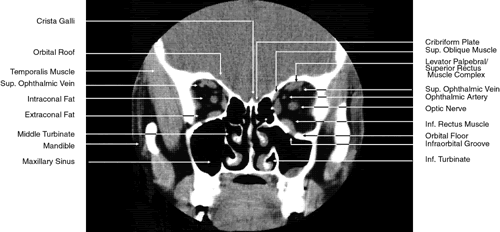

The globe is shown in Figure 12. The orbit and periorbital structures are shown in Figures 13 through 16, and the optic canal is shown in Figures 17 through 26. The cavernous sinus and optic chiasm are shown in Figures 27 and 28, and the posterior visual pathway and cranial nerves are shown in Figures 29 through 33.

Fig. 17. Coronal images through anterior orbit. A. Computed tomography scan. B. T1-weighted magnetic resonance imaging.

Fig. 18. Coronal images through midglobe. A. Computed tomography scan. B. T1-weighted magnetic resonance imaging.

Fig. 19. Coronal images through midorbit posterior to the globe. A. Computed tomography scan.B. T1-weighted magnetic resonance imaging.

Fig. 20. Coronal images through orbital apex. A. Computed tomography scan. B. T1-weighted magnetic resonance imaging. C. Anatomic section of a cadaver head at the level of the orbital apex.